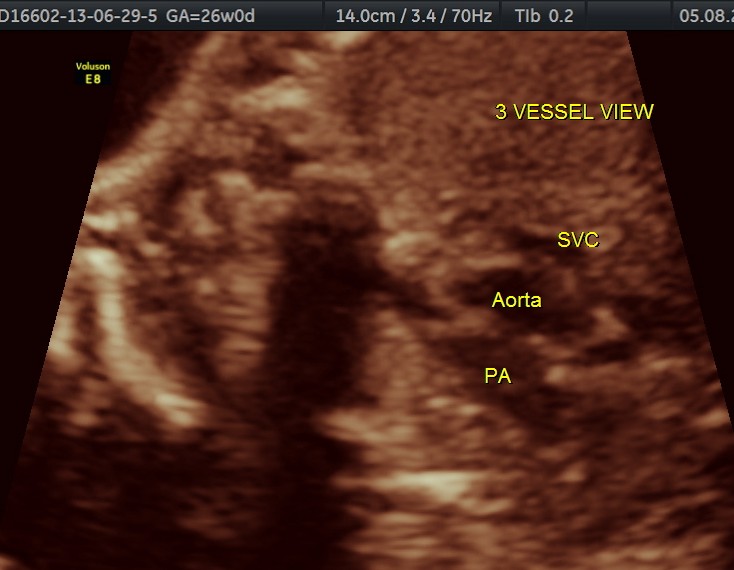

The following are of the 26 weeks gestation.